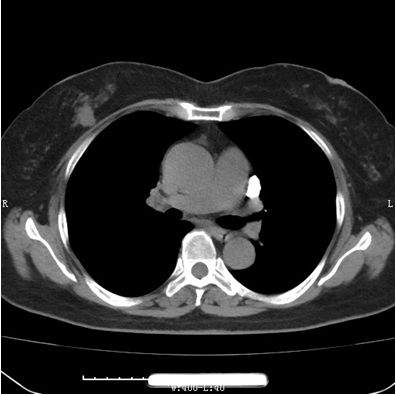

乳腺 CT 检查:乳腺疾病诊断的“全能高手”

乳腺 CT 检查,基于胸部 CT 检查对乳腺部位进行三维重建,一次检查就能获取两个部位的结果,避免了反复扫描和重复收费,为您节省时间和金钱。它在乳腺疾病诊断方面具有诸多优势:

高分辨率成像:CT 能够提供高分辨率的横断面图像,清晰呈现乳腺组织的细微结构,让微小病灶无所遁形,还能准确判断其对周围组织的侵犯情况,为后续治疗提供重要依据。

三维重建:扫描速度快,支持三维重建,医生可以更直观地观察病灶的形态、大小以及与周围组织的关系,大幅提升诊断的准确性,让治疗更加精准有效。

评估淋巴结转移:CT 可以清晰、全面地显示腋窝及纵隔淋巴结,为评估乳腺癌的淋巴结转移情况提供关键信息,帮助医生制定更合理的治疗方案。

引导穿刺活检:在 CT 引导下进行乳腺病灶的穿刺活检,能够提高取材的准确性,为诊断提供有力支持。

评估治疗效果:通过 CT 检查,可实时监测乳腺癌治疗后的变化,准确评估治疗效果,为后续治疗提供参考。